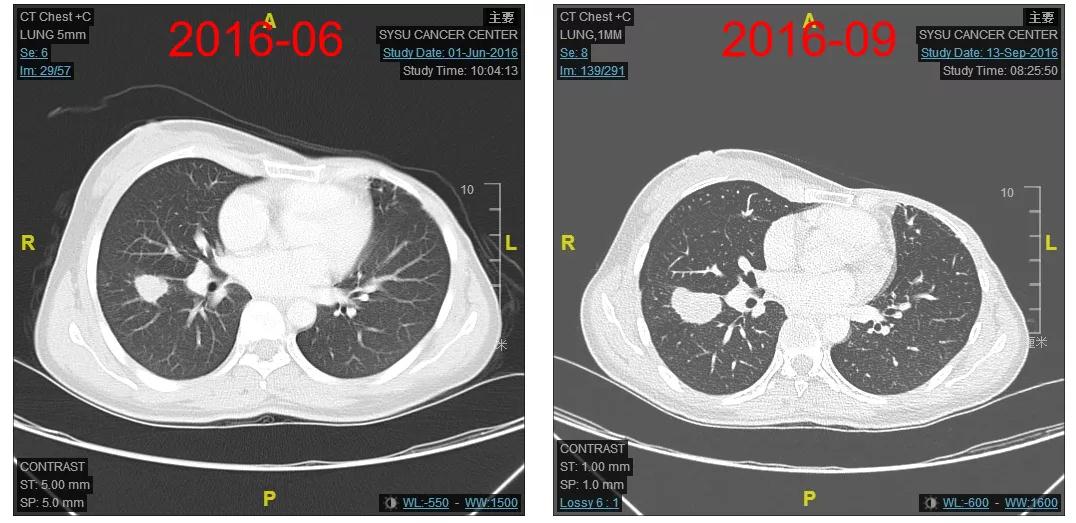

2016-12-06开始使用T-DM1(恩美曲妥珠单抗)方案治疗,首次疗效评估PR,后续最佳疗效CR(图2-3)。

图2

图3

患者为初诊IIIC期的HER2阳性乳腺癌,单靶曲妥珠单抗辅助治疗过程中发生多发肺转移;治疗采用T-DM1治疗获得迅速缓解(CR),PFS已近5年;用药过程中主要毒性集中在肝酶升高、血小板下降及中性粒细胞下降,均为1-2度,可对症处理或自行缓解;T-DM1一线治疗方案耐受性好,生活质量无影响。